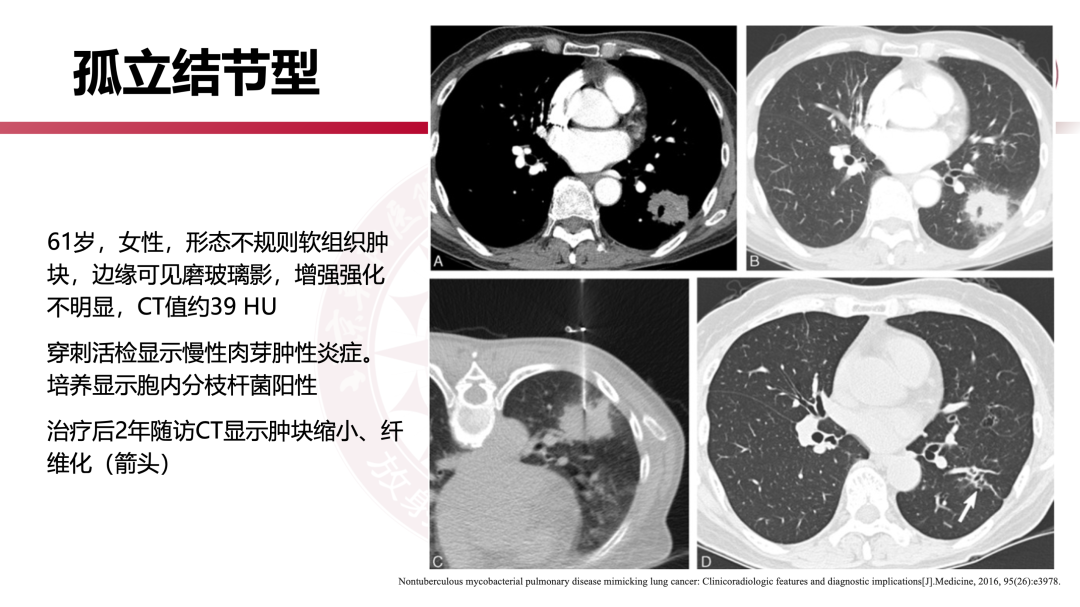

非结核分枝杆菌肺病有何影像学特点?|影像读片

来源 北京朝阳医院放射介入中心

课件提供 张子豪 翟晓力(放射)

点评专家 陈宁(放射)